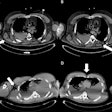

Team Sicily shines light on imaging of gunshot wounds